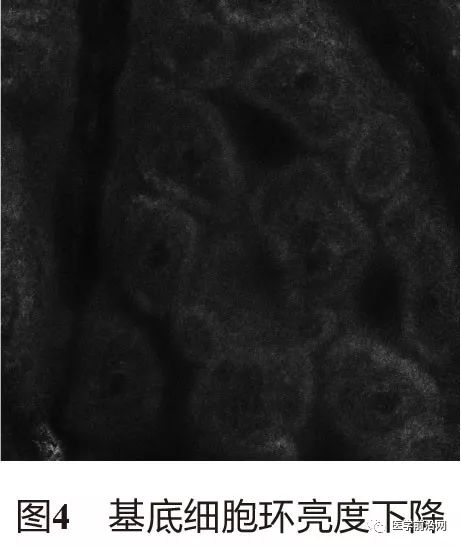

1.4 黑素细胞活性和定量 因黑素细胞损伤,基底细胞环的亮度下降(如界面皮炎)或消失(如白癜风),或因黑素细胞的黑素小体向角质形成细胞转运减少,DEJ和棘细胞层的亮度消失或减少(图4)。